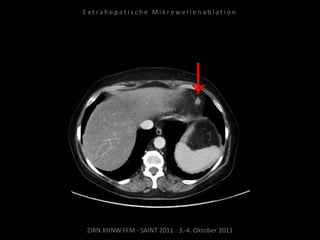

Bildgebung vor MWA:

CT 14.03.2011

Situation:

Nur 1 Metastase, diese ist jedoch

progredient. Kritische Lage in

Herznähe.

Ziel:

Destruktion der solitären Metastase

unter Schonung der Nachbar-

strukturen.

Indikation zur MWA:

Nachweis nur einer Metastase, diese

ist progredient, in der Größe gut zur

Ablation geeignet.

Ablation am 24.03.2010:

2 Nadelpositionen.